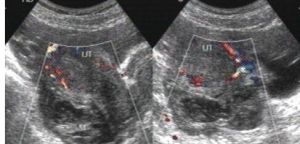

6.必要時行婦科B超、腹腔鏡檢查。

根據病史、臨床表現和檢查進行診斷。月經後半期突發下腹部疼痛,下腹部壓痛、反跳痛,婦科檢查後穹隆觸痛,一側附屬檔案區包塊伴壓痛。B超發現一側附屬檔案低回聲區,後穹隆穿刺抽出不凝血。鑑別診斷

卵子在輸卵管壺腹部受精,受精卵因某些原因在輸卵管被阻,而在輸卵管的某一部分著床、發育,發生輸卵管妊娠。多有停經史,臨床出現突然撕裂樣劇痛,自下腹一側開始向全腹擴散,陰道少量流血,暗紅色,可有蛻膜管型排出。盆腔檢查有宮頸舉痛,直腸子宮陷凹有腫塊。陰道後穹窿穿刺可抽出不凝血液。B超提示一側附屬檔案低回聲區,其內有妊娠囊。